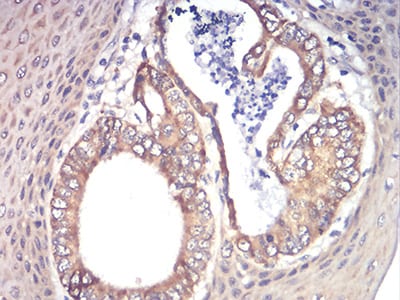

Immunohistochemical analysis of paraffin-embedded human brain tissues using RAD21 mouse mAb with DAB staining.

Immunohistochemical analysis of paraffin-embedded human esophageal cancer tissues using RAD21 mouse mAb with DAB staining.